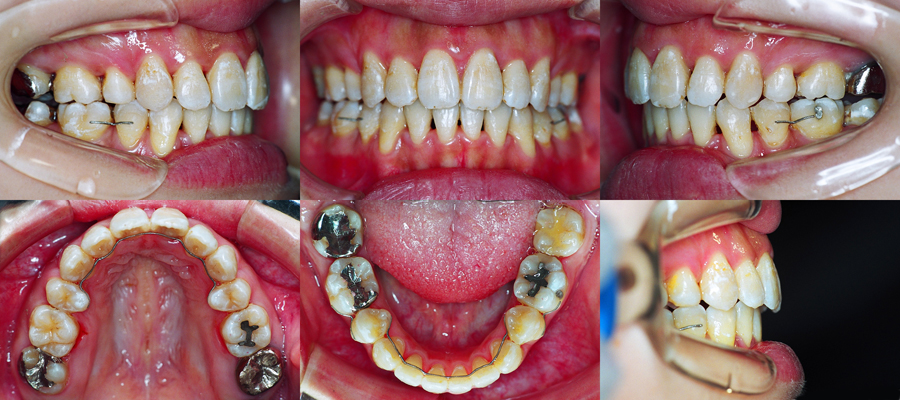

上下顎前歯部叢生と上顎歯列弓狭窄を伴う開咬

初診時

治療終了時

詳しい治療経過をご覧になられる場合は画像をクリックして下さい。